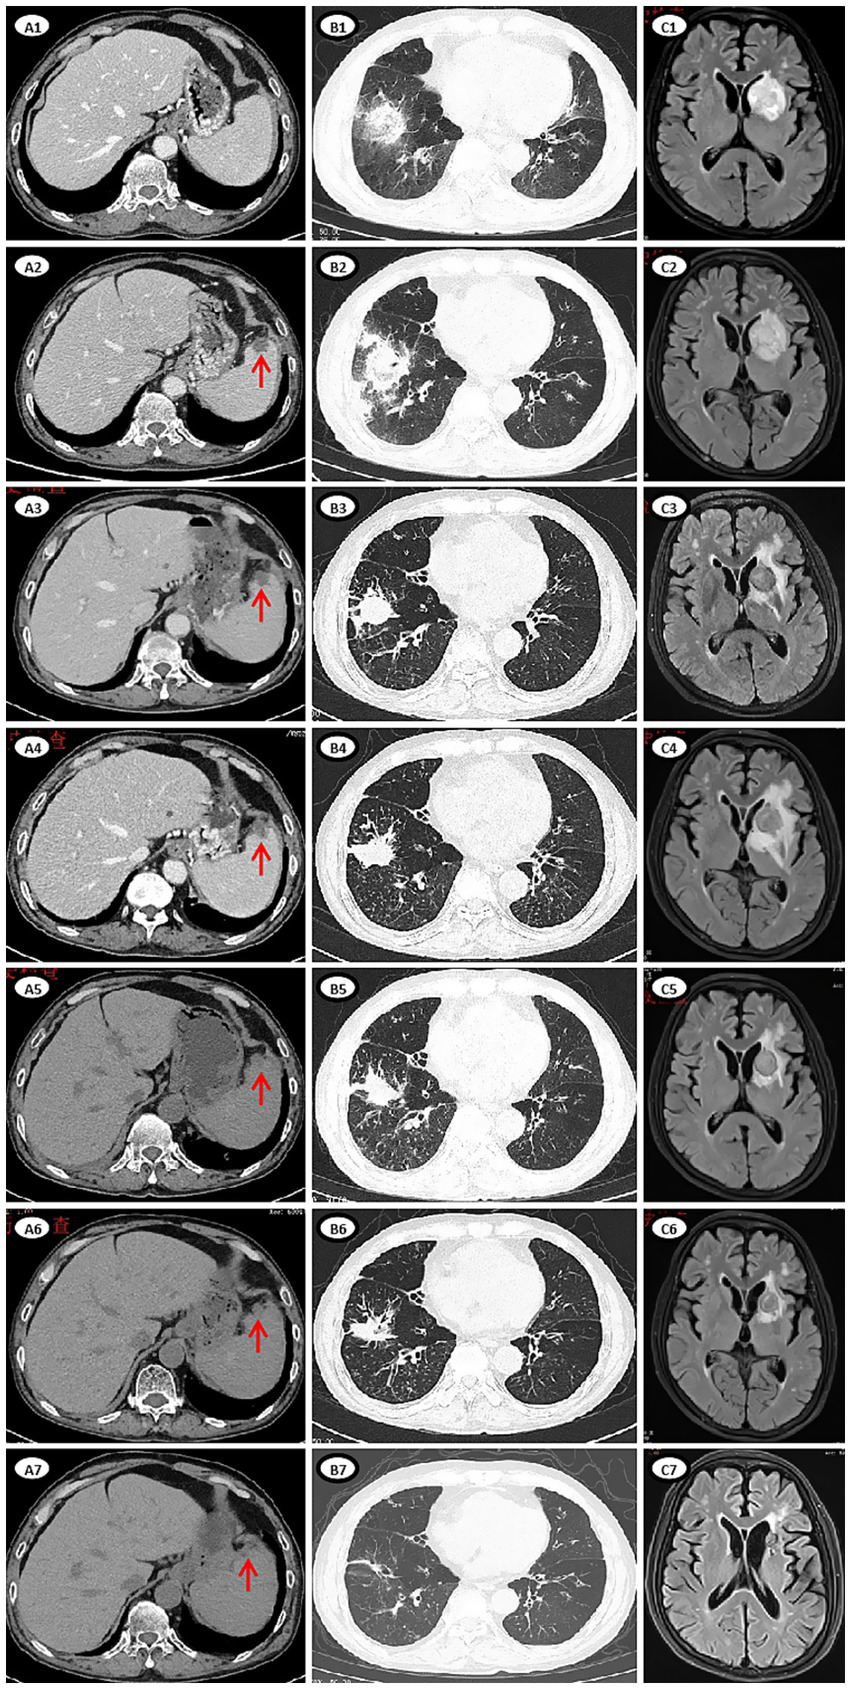

Figure 2

Imaging manifestations of lesions of mucormycosis during treatment. (A1–A7) CT images of abdomen. (A1) Day 10, no new lesion in the spleen. (A2) Day 24, multiple round low-density lesions in the spleen (red arrow), which appeared newly after the last chemotherapy. (A3) Day 74, some lesions were slightly reduced. (A4) Day 106, the lesions were slightly larger. (A5) Day 135, the lesions were smaller. (A6) Day 169, the lesions were smaller. (A7) Day 377, the lesions were no longer apparent. (B1–B7) CT images of chest. (B1) Day 17, multiple new nodules and consolidation in both lungs, extensive exudation in the right lower lung with a reversed halo sign, involving the right diaphragm. (B2) Day 27, the lesion in the right lower lung progressed. (B3) Day 75, a cavity formed and the extent of exudation was reduced. (B4) Day 119, the lesion was slightly progressed. (B5) Day 141. (B6) Day 187. (B7) Day 476. (C1–C7) MRI images of brain. (C1) Day 24, a patchy shadow (39 × 28.9 mm) in the left basal ganglia. (C2) Day 29, the lesion (41.9 × 30.3 mm) was enlarged. (C3) Day 79, size of the lesion (19.1 × 19.1 mm) reduced. (C4) Day 107, the lesion (21.3 × 21.2 mm) was slightly enlarged, the area of edema was enlarged. (C5) Day 138, size of the lesion (20.2 × 18.8 mm) and edema reduced. (C6) Day 192, size of the lesion (16.2 × 15.4 mm) and edema reduced. (C7) Day 644, size of the lesion (9.8 × 9.6 mm) decrease significantly.

On day 10, the patient developed abdominal pain in the right lower quadrant. A contrast-enhanced computed tomography (CT) scan of the abdomen revealed no abnormalities (Figure 2A1). On day 11, the patient developed a fever to 39.5°C without cough or chest tightness. Laboratory tests revealed a C-reactive protein (CRP) level of 76.3 mg/L and a procalcitonin level of 0.1 ng/mL. Empirical intravenous treatment with biapenem (0.6 g q12h) and vancomycin (1 g q12h) was initiated. The patient remained persisted fever at 39.5°C, causing weak enough to be bedridden. On day 14, empirical treatment of intravenous antibiotics was changed to biapenem combined with voriconazole (400 mg q12h) and tigecycline (100 mg q12h). However, the patient’s fever showed no remission. On day 16, we sent his peripheral blood sample for mNGS analysis. On day 17, the ANC increased to 1.24 × 109/L, and the abdominal pain subsided as well as the temperature recovered. However, the patient developed persistent hiccups, along with cough, chest tightness, and sputum with blood. A chest CT scan was performed, which revealed multiple new nodules and consolidation in the lungs, as well as extensive exudation in the right lower lung with a reversed halo sign, potentially involving the right diaphragm (Figure 2B1), suggesting fungal infection of the lungs. On day 18, the results of mNGS analysis of his peripheral blood sample revealed 31,206 reads of Rhizomucor pusillus, and no other pathogen was detected. Multiple pathogen cultures of blood, sputum and stool samples obtained at the onset of fever and during persist fever, had no positive result to support any pathogen infection. The procalcitonin, (1,3)-β-D-glucan, and galactomannan test of the patient’s samples was negative. Esophageal echocardiography was performed without any valvular vegetation. He was diagnosed with IM involving the lungs and diaphragm. The anti-fungal regimen was immediately changed to a combination of amphotericin B (AmB, escalated from 0.1 mg/kg to 0.8 mg/kg intravenously daily; meanwhile, 5 mg was inhaled q12h), posaconazole (POSA, 400 mg orally q12h), and caspofungin (CAS, 70 mg on the first day, followed by 50 mg daily). The patient’s dyspnea and abdominal pain gradually decreased.

On day 24, the patient presented with transient amnesia of recent events and one episode of fecal incontinence. Physical examination revealed a decline in functions of temporal and spatial orientation. The Glasgow Coma Scale score was 14 (E4V4M6). A brain MRI (Figure 2C1) was performed, which revealed a 39 × 28.9 mm mass in the left basal ganglia and new infarction foci in the left cerebral peduncle and the right cerebellar hemisphere. Moreover, another abdominal CT (Figure 2A2) scan revealed multiple new, rounded, low-density lesions in the spleen compared with the results of previous abdominal CT scan before chemotherapy, which suggested new splenic infarctions. However, no significant evidence of lymphoma progression was observed. On day 27, the patient experienced in continence of urine and feces again and concurrently answered incorrectly about his age. A subsequent chest CT scan revealed progression of the right lower lung lesion (Figure 2B2). A second brain MRI scan revealed an increased size of the mass in the left basal ganglia (Figure 2C2). Lumbar puncture was performed and normal cerebrospinal fluid (CSF) pressure was observed. Results of bacterial culture and mNGS test of CSF were negative. At the same time, we reexamined mNGS analysis of his peripheral blood sample, and no reads of Rhizomucor species were detected. On day 37, brain magnetic resonance spectroscopy (Figure 3) was conducted, indicating that the lesion in the left basal ganglia was nonneoplastic. After a discussion among experts in multiple disciplines, they agreed that the newly developed lesions in the lungs, CNS, and spleen were consistent with organ artery invasion by Mucor fungi and/or fungal emboli caused by Rhizomucor infection.

The patient was diagnosed with DM involving the lungs, diaphragm, CNS, and spleen. After continuous triple-drug antifungal treatment with AmB, POSA and CAS for 2 months, his symptoms of cough, chest tightness, hiccups, memory loss, fecal and urinary incontinence and abdominal pain were gradually relieved. After triple-drug antifungal therapy for about 3 months, follow-up imaging revealed a reduction in the size of the lesions in the spleen, lungs, and CNS, with no new lesions observed (Figures 2A3,B3,C3). Therefore, CAS treatment was stopped, and AmB (intravenous) treatment was continued for 8 months and POSA treatment was continued for 2.5 years (Figure 1).

Taking into account of a 6-week interruption of lymphoma treatment for the patient, we conducted chemotherapy as well as antifungal therapy to prevent lymphoma progression. On day 49, the patient received a ZR2 regimen, which included Zanubrutinib (ZAN, a Bruton’s tyrosine kinase inhibitor), 80 mg daily for 14 days; lenalidomide, 25 mg daily for 14 days; and rituximab, one 375 mg/m2 dose. On day 53, the patient developed a fever which was relieved by empirical treatment of sulbactam-cefoperazone. In addition, cytopenia occurred again after anti-lymphoma treatment. Although the patient received rituximab (375 mg/m2) monotherapy on day 87, he developed fever with cough and expectoration again on day 117. The CRP was 55.5 mg/L, and culture of sputum sample identified infection of Acinetobacter lwoffii. Piperacillin-tazobactam was initiated, resulting in symptoms relief. Even worse, after two cycles of chemotherapy, radiological imaging revealed that his DM-related lesions had progressed (Figures 2A4,B4,C4). Considering the patient’s weakness and persistent immunosuppressive state (lymphocyte count 0.53 × 109/L, globulin level 15.9 g/L), new strategies for lymphoma were urgently needed.

With the continued administration of AmB and POSA for anti-fungal treatment, we administered the first dose of PD-1 inhibitor (tislelizumab (TIS), 200 mg) on day 122 combined with long-term treatment with thalidomide (THD, 50 mg orally once nightly for 2 years) and ZAN (80 mg daily for 2 years) to control the lymphoma. Follow-up imaging revealed a reduction in lesion size (Figures 2A5,B5,C5). On days 148 and 177, we administered the second (200 mg) and third (100 mg, reduced by half owing to low blood cell counts) doses of TIS. Follow-up imaging indicated a reduction in lesion size in the lungs and CNS, and a slight reduction in size of the spleen lesion (Figures 2A6,B6,C6). On day 199, the fourth dose of TIS was administered at 100 mg. On day 240, AmB was discontinued because the cumulative dose exceeded 3 g, and POSA was continued as long-term antifungal therapy. On days 259, 280, and 318, the fifth, sixth, and seventh doses of TIS were administered at doses of 100 mg, 200 mg, and 200 mg, respectively. Follow-up imaging assessments revealed continuous reduction of all the fungal lesions, while the size of the lymphoma lesions was stable.

During the period of TIS administration every 3–8 weeks in combination with ZAN and THD, there were occasional episodes of slightly low blood counts, but no severe infections occurred. His fungal lesions in the spleen, lungs and CNS stopped shrinking at 12, 15, and 20 months, respectively, after the initiation of antifungal therapy (Figures 2A7,B7,C7). PET/CT revealed complete remission of the lymphoma 15 months and 27 months after the diagnosis of mucormycosis. At this time, the patient’s physical condition had significantly improved. To achieve better long-term survival, autologous HSCT was performed at 28 months after the diagnosis of mucormycosis. THD and ZAN were withdrawn at autologous HSCT for a total of 2 years treatment, and POSA continued. The process of autologous HSCT was successful, and no infections occurred. POSA was continued for half a year after HSCT. The patient was subsequently regularly followed up in the outpatient clinic for 2 years, with normal organ function, good physical status, and all lesions either caused by lymphoma or by mucormycosis almost disappeared.